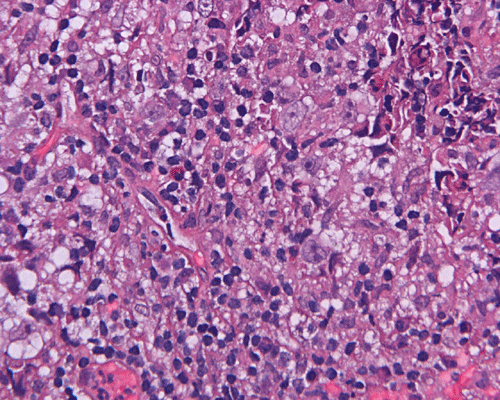

Paraffin sections: The entire volume of the tissue is made up of a granulomatous inflammation with poorly formed granuloma (Panel F, G, and H). The density of the lymphocytes is variable in different areas. In some areas, there is a rather intense lymphocytic infiltration accompanied by scant atypical cells with enlarged nulcei and prominent nucleoli (arrows in Panel I and J, Panel J is a higher magnification of Panel I). These atypical cells are quite easy to be missed. No microorganisms were identified by acid fast stain, PAS stain or GMS stain. The lymphocytes but not the atypical cells are positive for CD20 (Panel K) or CD3 (Panel L). The granulomatous background is strongly positive for CD68 (Panel M). Only rather faint positive staining for placental alkaline phosphatase (PLAP) is demonstrated and the interpretation is difficult as they are present in areas with crush artifact (Panel N). Many of the large, atypical cells are positive for CD117 (c-kit) (Panel O).

Intracranial germinoma is histologically identical to ovarian dysgerminoma and testicular seminoma. There is a tendency to infiltrate adjacent structures and to spread throughout the ependyma, the ventricular system and subarachnoid spaces. Microscopically, they consist of nests, lobules, cords, and/or sheets of large round tumor cells with well-defined borders, clear to pale cytoplasm with artifactual vacuolization, round and centrally located nuclei with open chromatin and prominent round or bar-shaped nucleoli. The cytoplasm is glycogen-rich, making these cells periodic acid-Schiff (PAS)–positive and diastase sensitive. These tumor cells are mitotically active. Atypical mitosis, however, is not a common finding. Necrosis is usually not prominent. In the most classic histologic picture, clusters and cords of large germinoma cells are separated by a dense, lymphocytic infiltration admixed with some macrophages and a delicate fibrovascular network. Plasma cells may be found. At medium-power magnification with hematoxylin and eosin stain, the contrast between the smaller, darkly staining lymphocytes and the larger, pale staining cytoplasm of neoplastic cells is virtually pathognomonic. The amount of inflammatory cells can have wide variations among different tumors. In some occasions, the large germinoma cells are difficult to be found and the overall picture may suggest a lymphoma. Syncytiotrophoblastic cells can also be present. These cells should not be mistaken as evidence of choriocarcarcinoma.

Germinomas can elicit an atypical gliosis in the surrounding glial tissue which may be confused with malignant glial neoplasms. This is true particularly of specimens taken from the periphery of the germinoma. The tumor may appear as a desmoplastic tumor. The inflammatory response may be problematic in reaching a histologic diagnosis, especially in small biopsies, as macrophages can be difficult to distinguish from a non-seminomatous neoplastic component.

Granulomatous changes are common findings in germinomas and intracranial germinomas follow this general trend 3, 4, 5. It can be extensive. This feature is particularly problematic in neuropathologic when stereotactic biopsy is performed and the amount of tissue available for examination is limited as illustrated in this case. During intraoperative consultations, a frozen section diagnosis of granulomatous inflammation should prompt additional sampling as isolated granulomatous inflammation of infectious origin and sarcodosis are quite uncommon in the pineal gland.